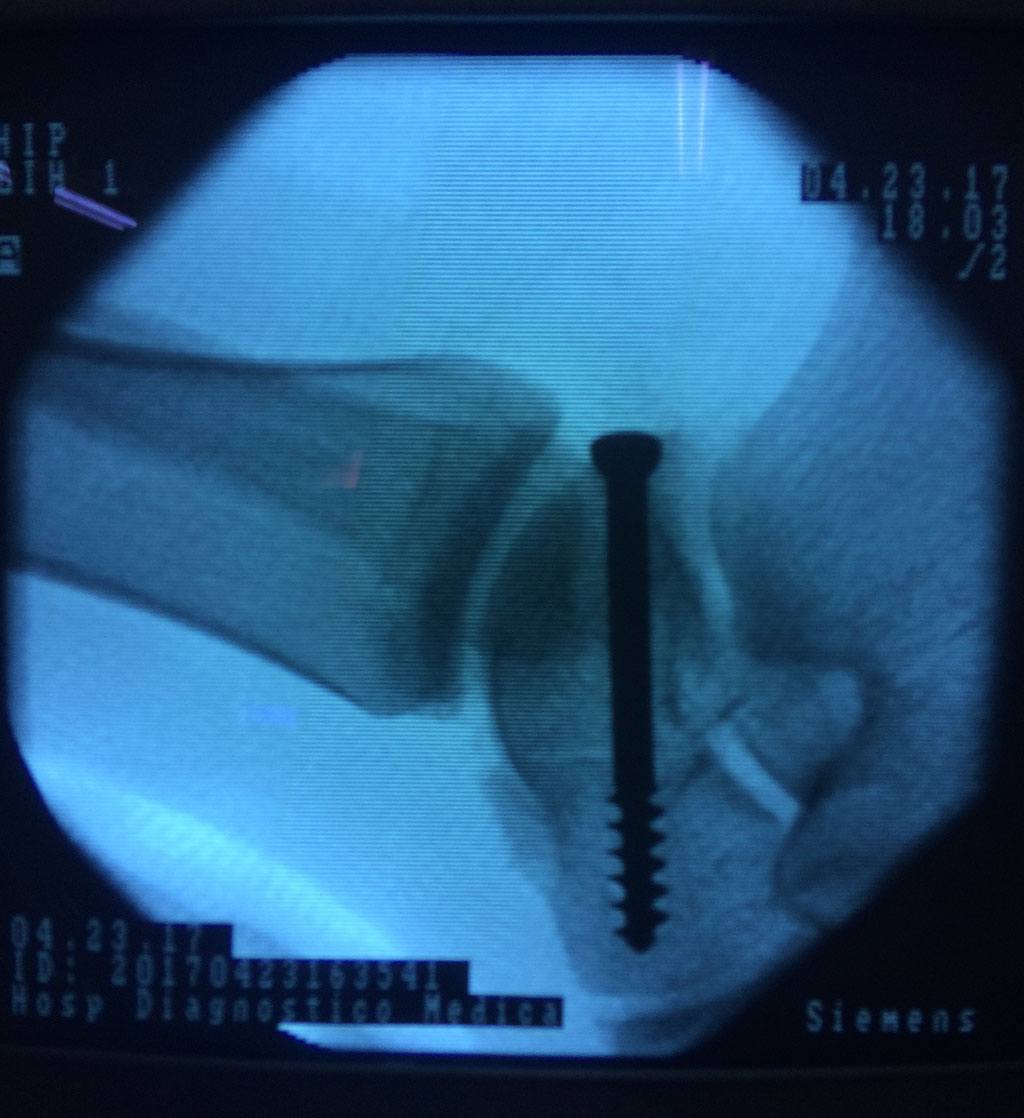

Cuando se necesita cirugía, es probable que esta implique el uso de clavijas de metal, tornillos o placas para sostener los huesos en su lugar mientras la fractura se consolida. Los elementos de soporte pueden ser temporales o permanentes.